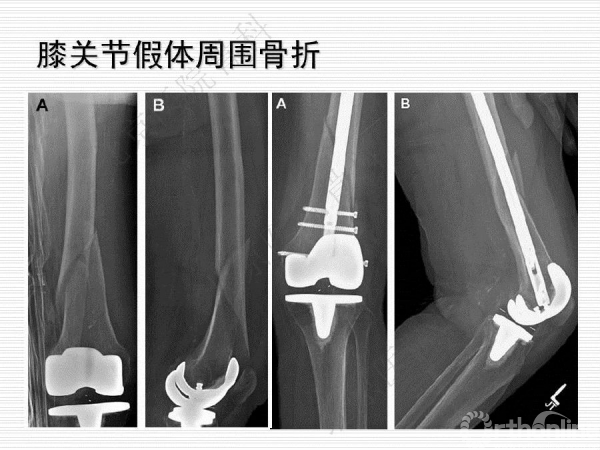

膝关节假体周围骨质疏松骨折1例

骨质疏松性骨折与创伤性骨折不同,是基于全身骨质疏松存在的一个局部骨组织病变,是骨强度下降的体现,也是骨质疏松症的最终结果。骨质疏松骨折是常见病、多发病,严重威胁中老年人身体健康,由此引起的骨质疏松性骨折,除了给患者本人造成极大的痛苦外,也给社会和家庭造成了沉重的经济和生活负担。来自北京医院骨科纪泉教授为我们带来一例经典的《膝关节假体周围骨质疏松骨折》病例,遂抗骨质疏松治疗预防再次骨折,任重而道远!